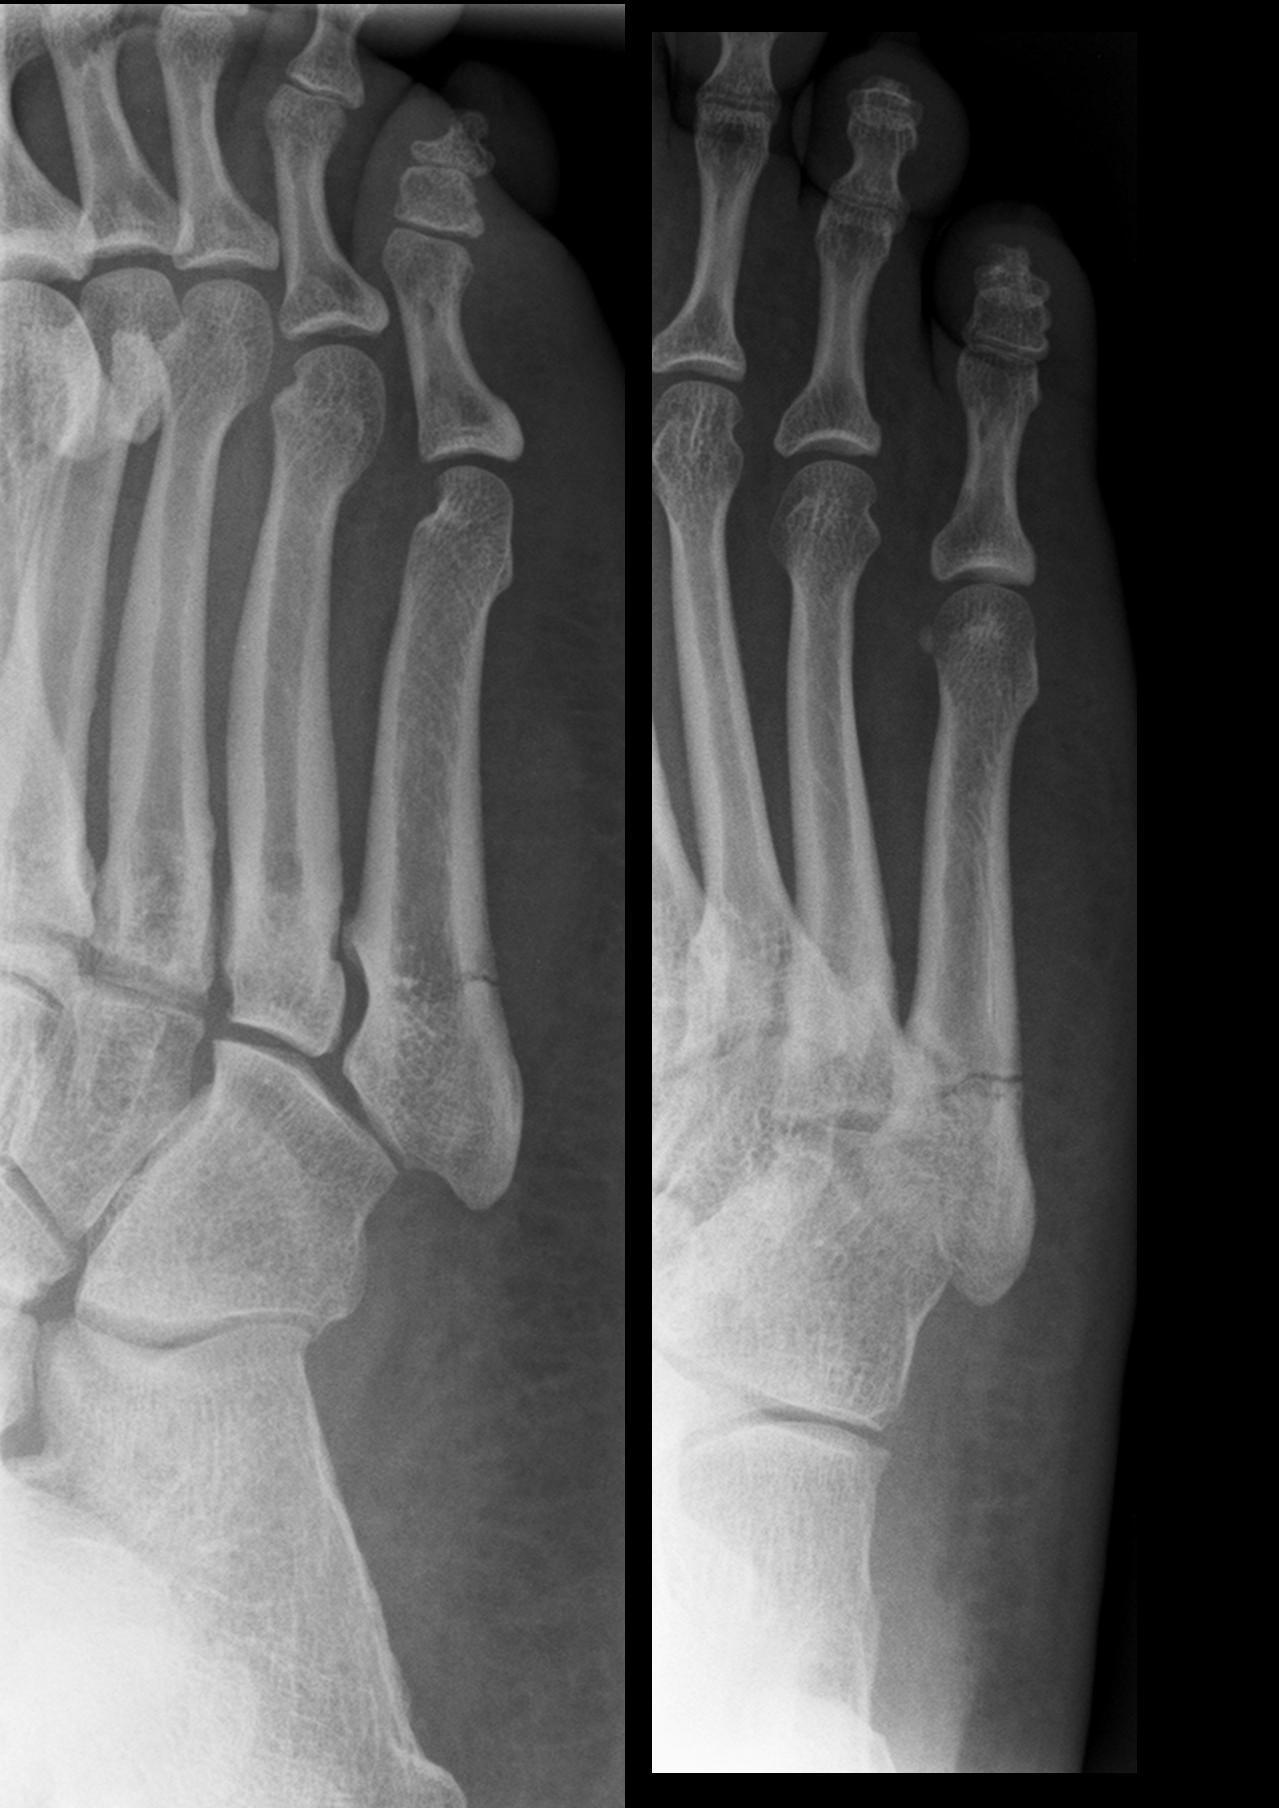

Fracture de metatarsien

Si fracture de la base du 5ème métatarsien (fracture de Jones ou pseudo-Jones) :